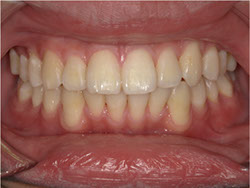

1期治療でスケルトンタイプの拡大装置で歯列拡大後、上下第一小臼歯を抜歯して口元もキレイになりました。

矯正終了後